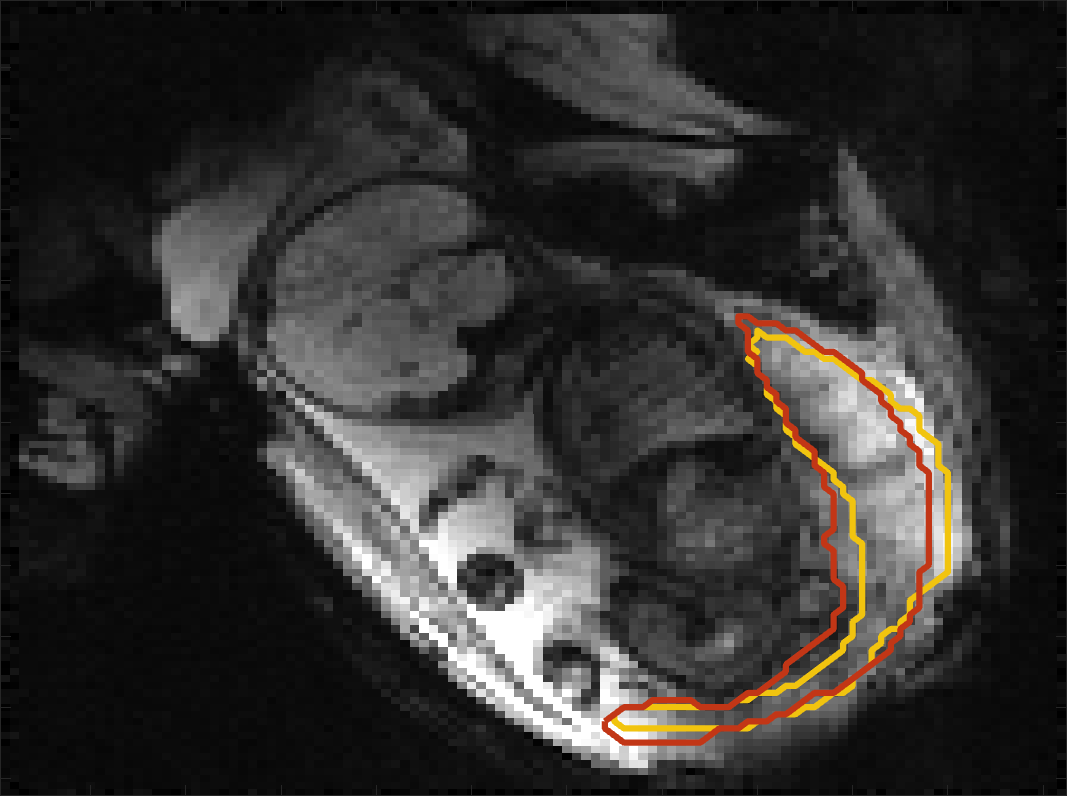

BOLD Time Series Evaluation

Figure 5 presents example predicted segmentations at multiple points in the BOLD MRI time series for subjects. The predicted segmentations are robust to large fetal deformations and placental signal changes. Figure 6 (top) presents distributions of Dice score between predicted label maps of consecutive frames in the BOLD time series for all subjects in the test set. Distributions have high medians (Dice ) for all but one case, with high density at high Dice scores (Dice ). Dice differences are highly affected by fetal and maternal motion that cause placental deformation. We visually verified that modest drops in Dice () were mainly due to fetal motion, but subjects had a small number of frames with large drops (Dice ) that were caused by errors in the produced label maps. Figure 6 (bottom) shows D models of failed segmentations from two subjects from frames with Dice . Our model omitted parts of the placenta for Subject and added a large region for Subject . In practice, these failures ocurred in a small number of frames, of frames for Subject and of frames for Subject . Overall, predicted label maps are consistent between consecutive volumes of the MRI time series, achieving a Dice of and a BOLD difference of . The small differences between the relative mean-BOLD values suggest these produced segmentations may be suitable for research studies assessing placental function.